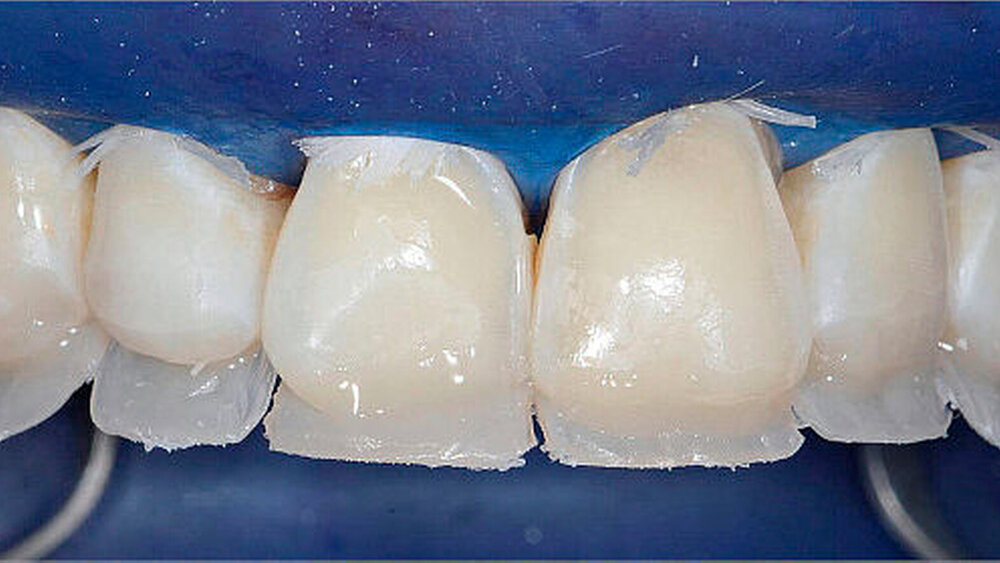

Nach Kofferdamapplikation wurde die Bisshebung im Seitenzahnbereich mit direkten okklusalen Kompositaufbauten (Tabletops) mit dem Kompositmaterial Filtek Supreme XTE (3M Espe) und dem Adhäsivsystem Optibond FL (Kerr) durchgeführt. Der Aufbau erfolgte dabei Zahn für Zahn unter Zuhilfenahme der Übertragungsschienen. Um ein interdentales Verblocken zu verhindern, wurden jeweils die Nachbarzähne der zu restaurierenden Zähne mit Teflonband isoliert (Abbildung 3).